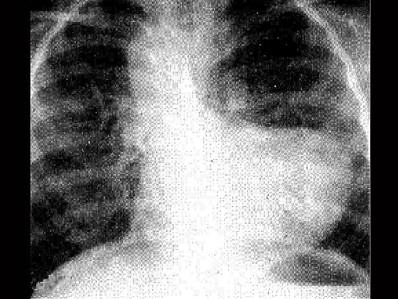

问题 法洛四联症时X线检查典型表现如图,下列哪一项描述正确 ( )

选项 A、升主动脉扩大 B、肺动脉段突出 C、右位主动脉弓 D、肺野充血 E、心影大小正常或稍增大,前后位心影呈“靴状”

答案 E